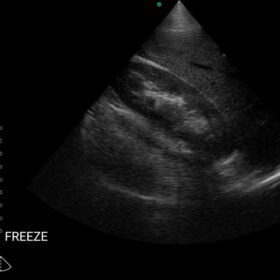

Cardio 2D, Color and PW doppler